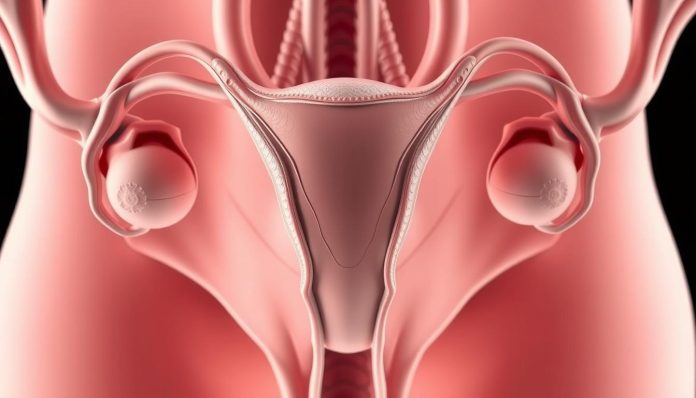

تعريف المبايض وموقعها في جسم المرأة

المبايض هو جزء مهم من جسم المرأة. يلعب دورًا كبيرًا في صحة المرأة. تقع هذه الغدد في منطقة حوض المرأة.

الموقع التشريحي للمبايض

المبايض تقع في جانبي الرحم. محاطة بأربطة تثبتها في مكانها. هذا يساعد في حماية المبايض وضمان عملها.

حجم وشكل المبايض الطبيعي

حجم المبايض يتراوح بين 3-5 سم في الطول و1.5-3 سم في العرض. لها شكل بيضاوي ولون أبيض مائل للرمادي. أي تغيرات كبيرة قد تشير إلى مشاكل صحية.

- الطول الطبيعي: 3-5 سم

- العرض الطبيعي: 1.5-3 سم

- الشكل: بيضاوي

التركيب النسيجي للمبايض

المبايض تتكون من طبقتين: قشرة خارجية ولب داخلي. القشرة تحتوي على البويضات ولب غني بالأوعية الدموية. هذا يساعد في إنتاج الهرمونات وحماية المبايض.

فهم التركيب التشريحي للمبايض مهم للصحة. يساعد النساء على متابعة صحتهن الإنجابية.